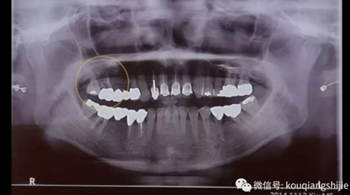

我們可以看到#17,18的牙周炎非常嚴(yán)重

從CT上我們可以看到骨破壞非常嚴(yán)重

拔牙后也將拔牙窩內(nèi)的黏膜提拉上來(lái)

十周之后我們可以看到黏膜組織沒(méi)有出現(xiàn)凹陷

翻瓣之后可以看到形成的充足的骨量